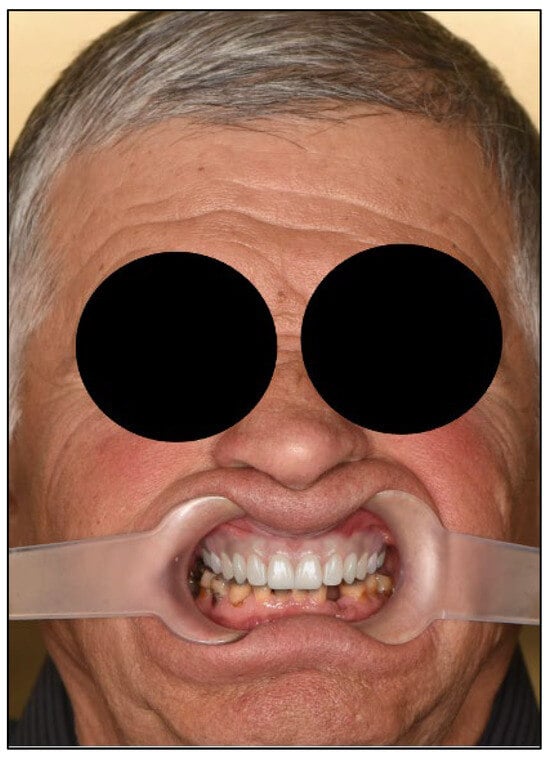

Figure 4.

Facial analysis. Extraoral photography with lip retractors to enhance view of the teeth.